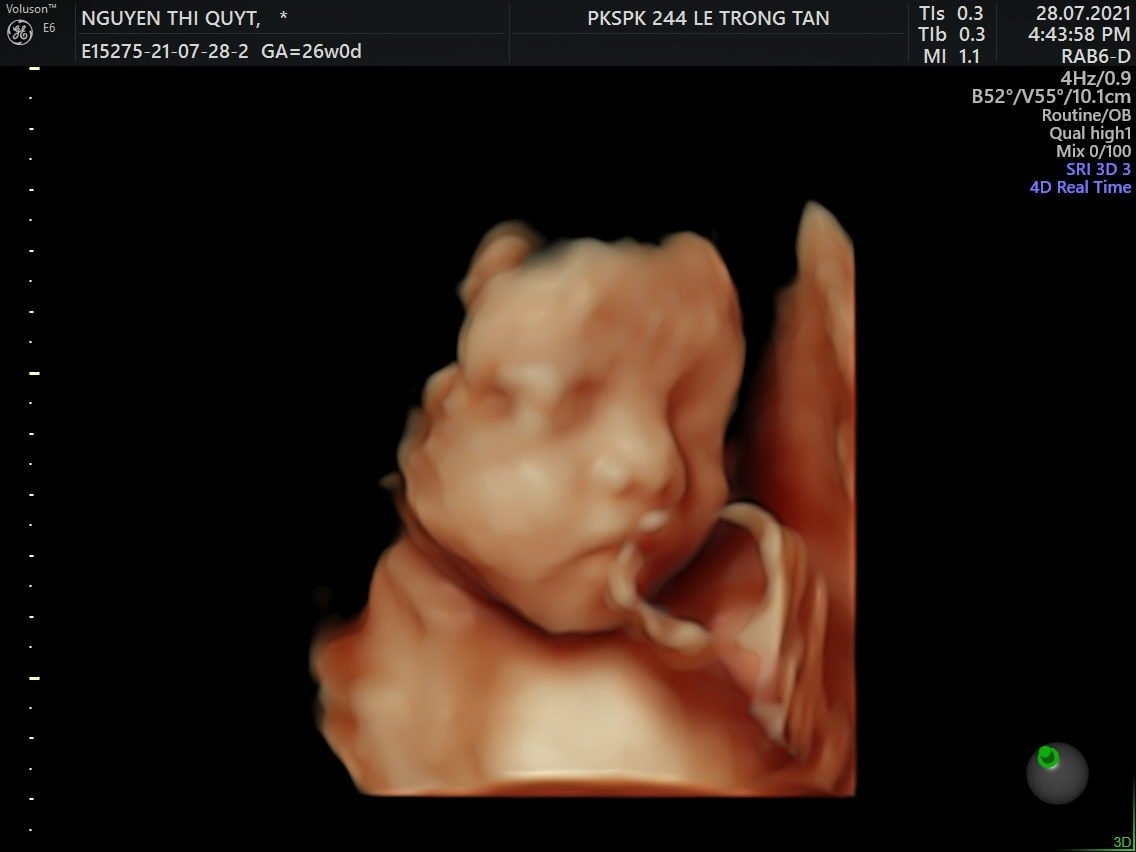

Ps: Coca lúc 26w ❤️ từ lúc mang bầu đến giờ có mỗi lần nàng cho xem mặt đấy các mom ạ. Không lấy tay che thì cũng úp mặt vào bụng mẹ😓